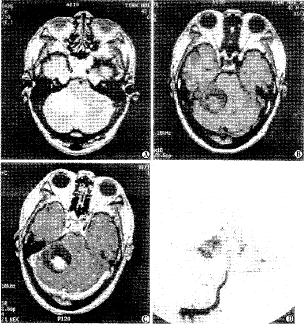

图4 A、B. T2、T1像右侧小脑半球可见囊实质型血管网质细胞瘤 B、C. T1增强像右侧小脑半球可见囊实质型肿瘤增强,左侧小脑半球可见斑块样实质增强 D. DSA右侧椎动脉正位像可见双侧小脑半球肿瘤染色

2.4 DSA检查结果 41人行选择性脑动脉造影。39例行左侧颈内动脉造影,39例行右颈内动脉造影,39例行左椎动脉造影,35例行右椎动脉造影,3例行颈外动脉造影。均可见肿瘤染色。实质型14例,囊实质型14例。肿瘤实质部分染色清晰,其内可见不染色的囊。可见脑内动脉增粗供血。21例可见肿瘤静脉引流。囊结节型13例,肿瘤囊壁结节染色较浅,未见肿瘤囊腔周边染色,囊腔可挤压周围血管引起占位征。无静脉引流。3例可见脑膜血管增粗供血。颈髓上部病变3例,可见双侧椎动脉的小脑后下动脉及双侧上颈部椎间孔动脉增粗供血,均可见静脉引流。3例可见多发病变,2例同MR。1例为双侧小脑半球实质型肿瘤。